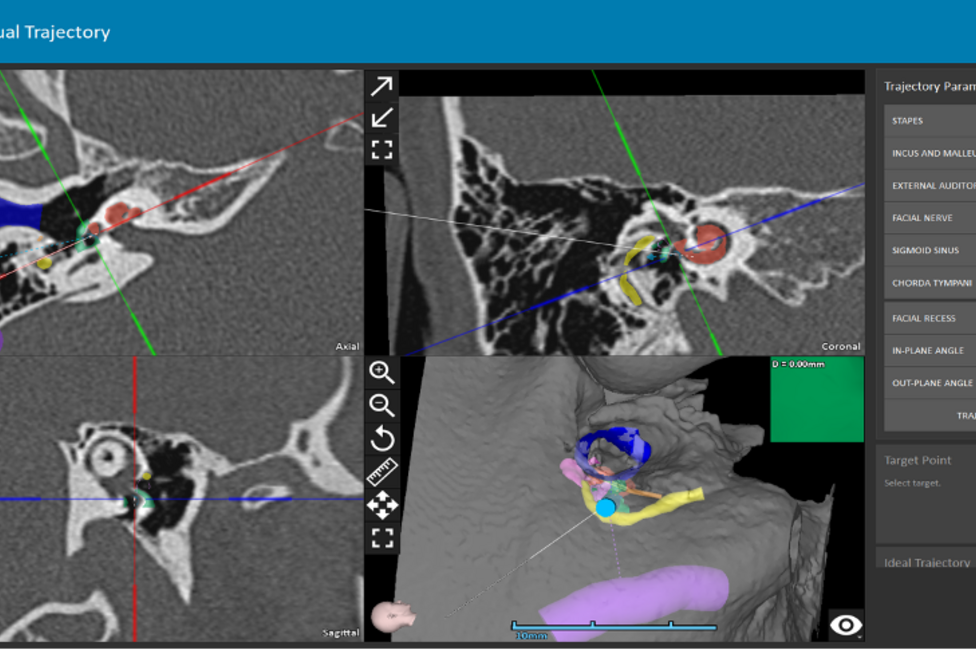

Schließlich wird mit dem:der Patient:in gemeinsam entschieden, ob eine klassische Mittelohroperation (Tympanoplastik), eine Stapesplastik, ein Hörimplantat (z.B. Cochlea-Implantat) oder ein konventionelles Hörgerät die besten Aussichten auf Erfolg hat.